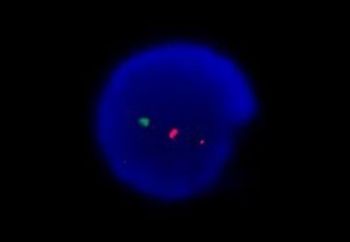

Based on data from the CARTITUDE-1, the BCMA-targeting CAR T-cell therapy ciltacabtagene autoleucel moves forward towards regulatory approval in multiple myeloma.

An affinity-tuned CAR T-cell product will be evaluated in thyroid cancer with a fast track designation from the FDA.